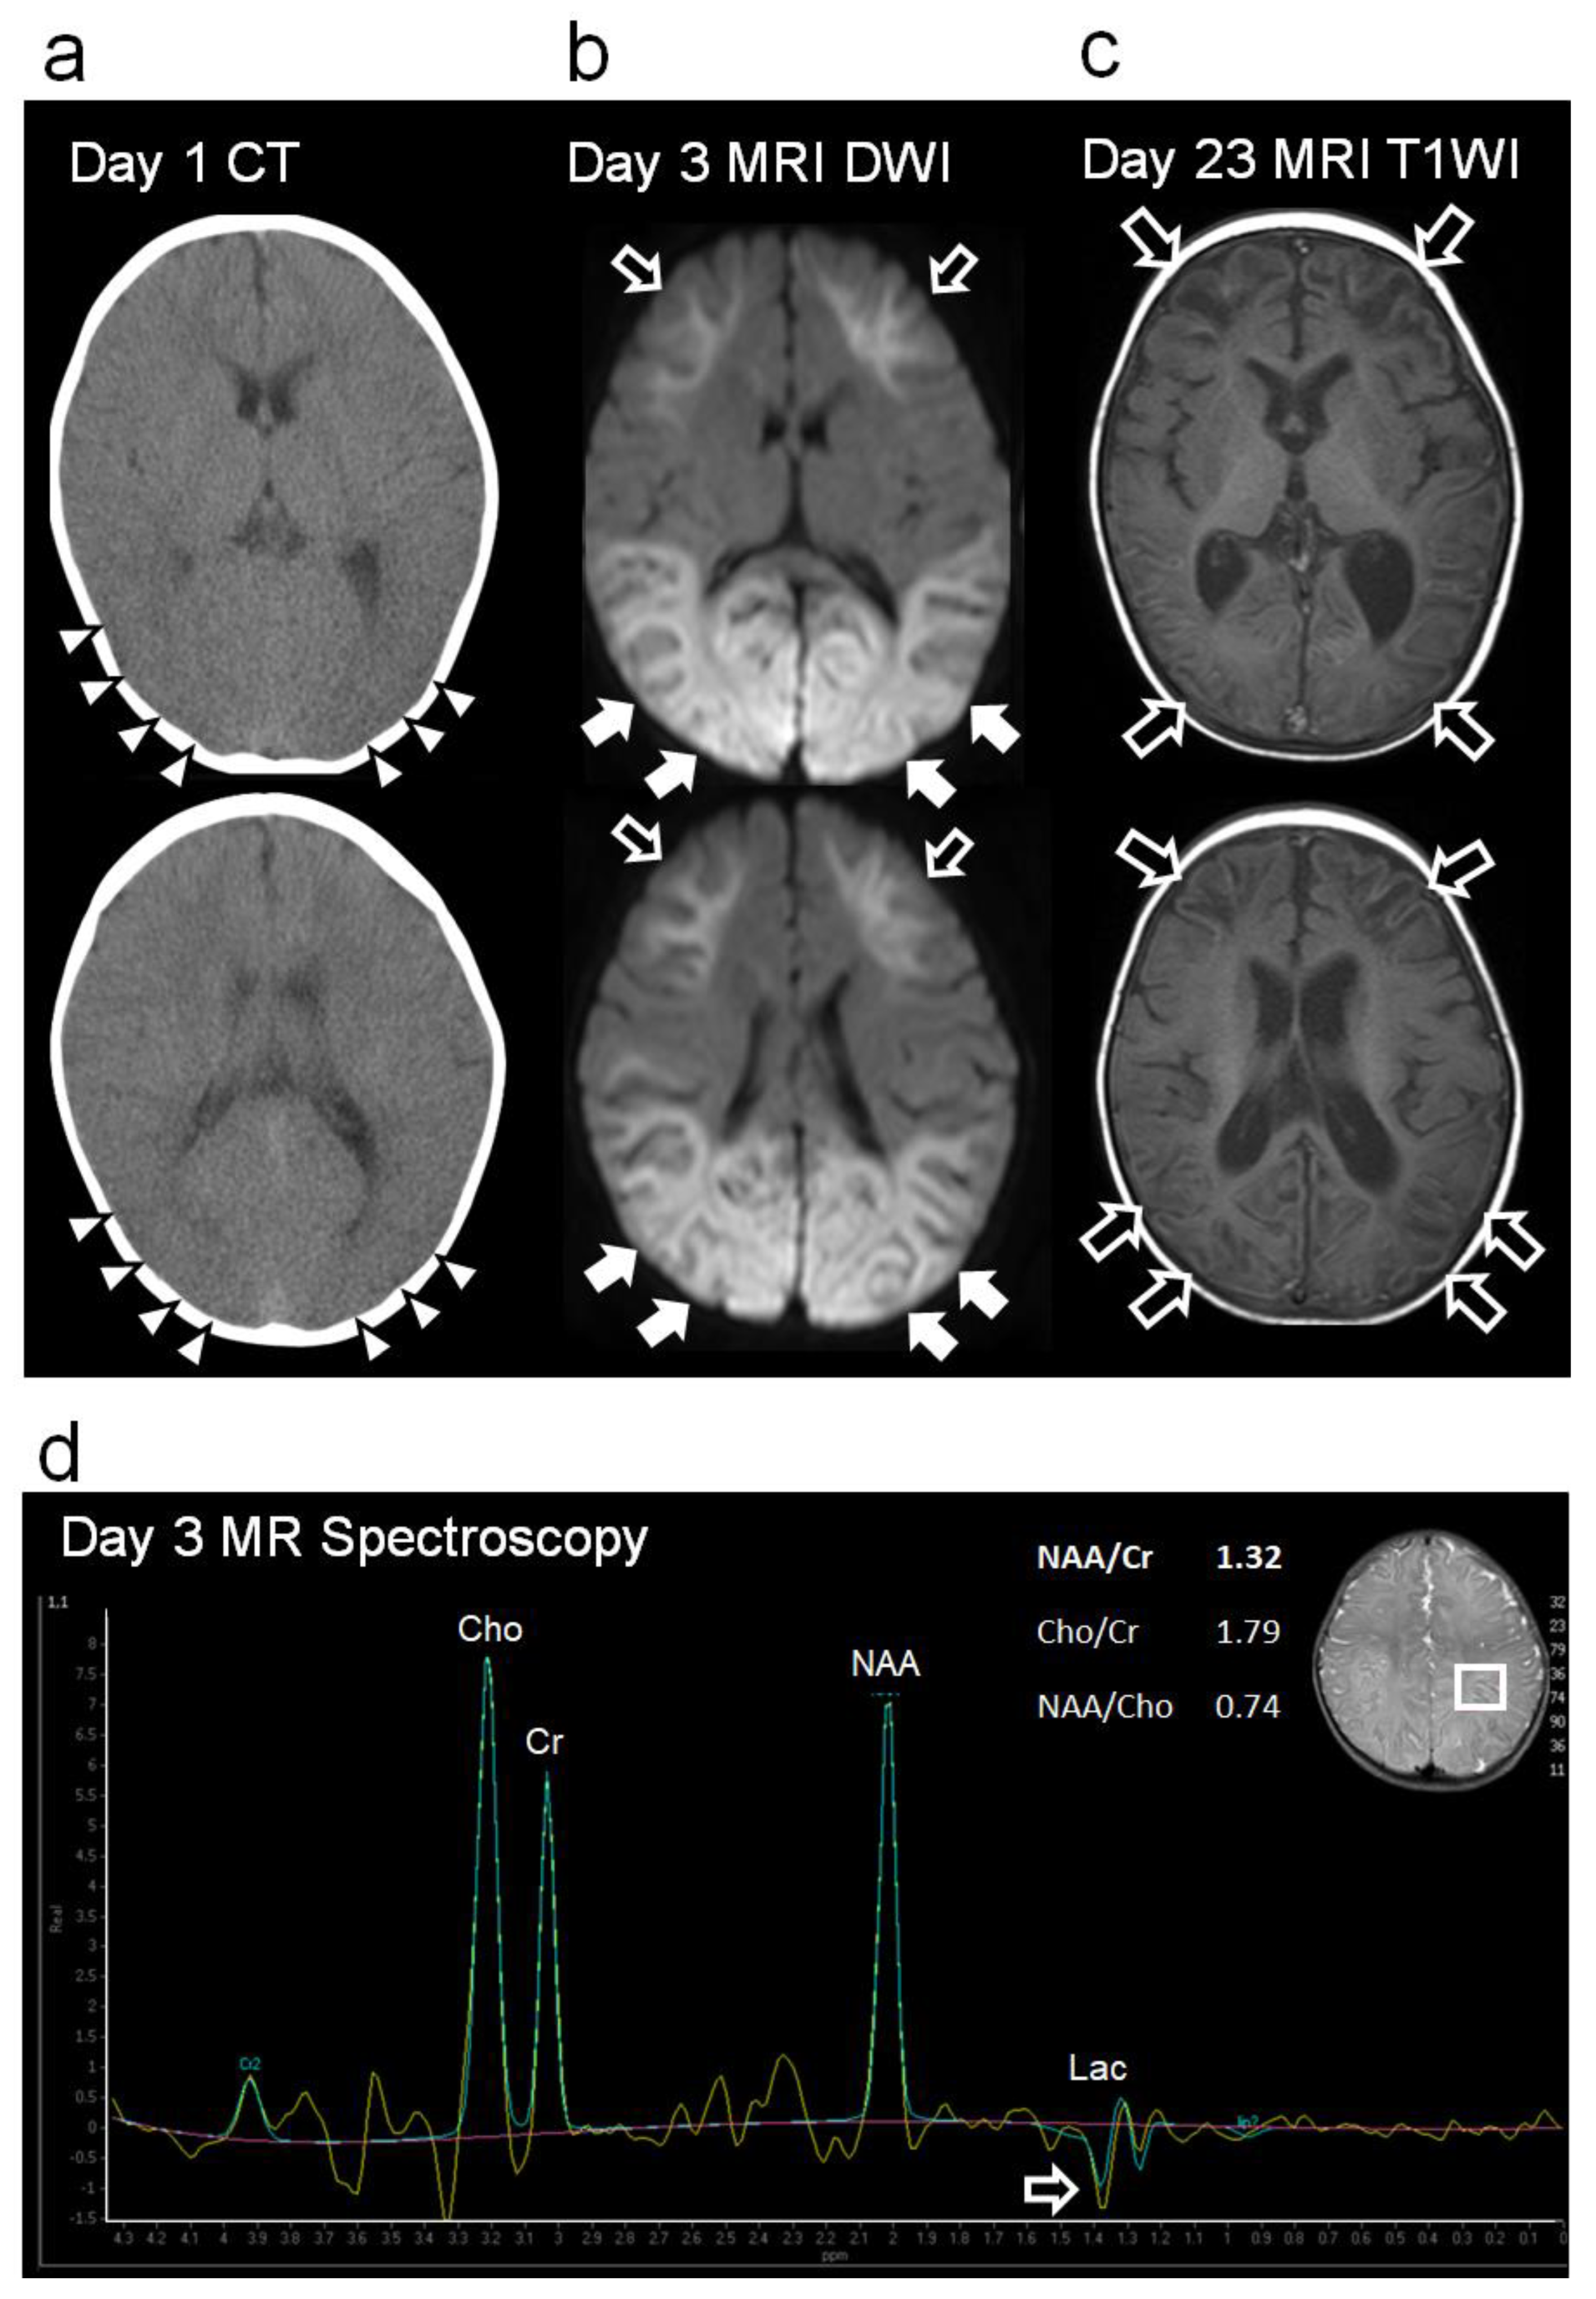

Figure 2a).

On day 3, however, the patient’s consciousness level deteriorated to E3V2M4 (GCS), and she experienced a cluster of generalized tonic–clonic seizures. EEG revealed diffuse spike-and-wave complexes predominantly in the occipital region (

Figure 3d). Head MRI-DWI on the same day showed reduced diffusion in the subcortical areas, except the perirolandic regions invoking BTA with central sparing (

Figure 2b). In the occipital and lateral temporal lobes, DWI high-signal areas extended into the cortex as well as the subcortex (

Figure 2b). Magnetic resonance spectroscopy (MRS) (TE = 144 msec) revealed only a slightly inverted lactate peak (

Figure 2d).

Figure 1). Head MRI T2-weighted imaging on day 23 revealed laminar necrosis in the frontal and occipital cortices, thinning of the corpus callosum, and a decrease in the volume of the bilateral cerebral hemispheres, basal ganglia, and hippocampi (

Figure 2c). One year after onset, at the age of 1.5 years, she experienced visual cognitive dysfunction but could utter ten meaningful words and walk without assistance.

A slight lactate peak on MRS was observed in our case, which indicated acute hypoxia and cerebral ischemia reflecting anaerobic brain metabolism, suggesting that hypoxia was already present at the time of onset [

9];

Cortical laminar necrosis, which manifests as subacute, curvilinear, hyperintense cortical lesions on T1-weighted imaging, indicated selective hypoxic necrosis of cortical layers 3, 5, and 6, which are particularly vulnerable to hypoxia, as was observed in our case [

10];

Figure 2.

Changes in imaging findings during the acute to subacute phases. (a) Head CT (Day 1): Diffuse cerebral edema and indistinct corticomedullary borders (white arrowhead). (b) Head MRI-DWI (Day 3): High-intensity lesions can be seen extending throughout the subcortical white matter and deep white matter of the frontal lobes (bright tree appearance, black arrows). In the occipital and lateral temporal lobes, the high-signal extends to the cortex (white arrows). No high-intensity area was observed around the central cerebral sulcus (central sparing). (c) Head MRI T1-weighted imaging (T1WI) during the subacute period (day 23). Curvilinear hyperintense lesions were observed mainly in the cortex of the frontal and occipital lobes (cortical laminar necrosis, black arrows). Significantly decreased volumes of the cerebral cortex hemispheres, basal ganglia, hippocampi, and cerebral corpus callosum were also observed. (d) Proton MR spectroscopy of the parietal lobe (volume of interest, 15x20x20 mm3, echo time=144 msec, repetition time=2000 msec) on day 3. No specific spectrum was observed, except for a slightly inverted lactate peak (black arrow). Lac, lactate; NAA, N-acetylaspartate; Cr, creatine; Cho, choline.